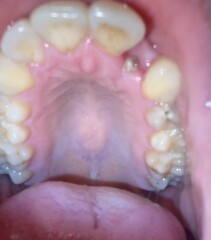

I had a tooth extracted 7 days ago now everything has been fine but tonite I started to get a mild throbbing pain on the extracted tooth I have salt washed and it was still throbbing. I can’t tell if I have dry socket or if it is the white granulating healing stage. I’m also concerned as I thought by day 7 the hole should be starting to close up please can anyone help